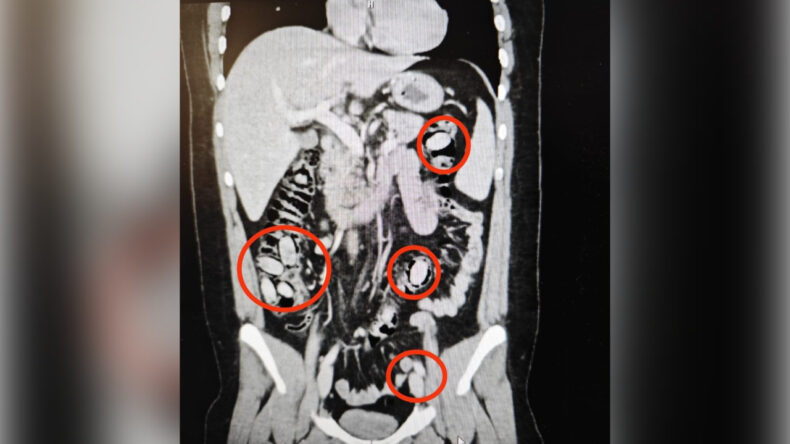

Hastanede yapılan röntgen görüntülerinde, S.A.'nın midesinde toplamda 44 kapsül bulunduğu belirlendi.

Eskişehir Cumhuriyet Başsavcılığı'nın talimatıyla acilen cerrahi müdahaleye alınan S.A.'nın midesinden bu kapsüller çıkarıldı.